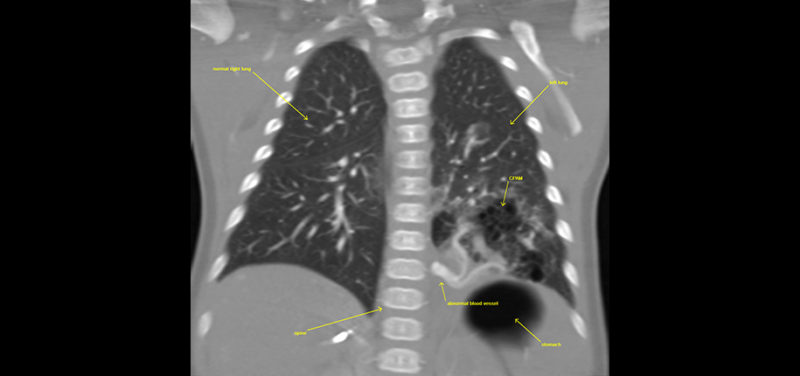

For example, one of our cardiothoracic radiologists, a doctor who looks at images of the heart, lungs and airway, is working with one of our fellows to see if there is a better way to look at infants with a lung abnormality known as CPAM (congenital pulmonary airway malformation). A CPAM is an abnormality of lung development that can make it difficult for a baby to breathe when he or she is born. A CPAM can also rarely lead to cancer if it is not removed. As a result, surgery is usually necessary to remove the CPAM.

Before surgery, a CT scan is often requested to see the size and location of the CPAM and to see if there are any abnormal blood vessels flowing into or out of the CPAM. This CT scan provides important information to the surgeon, which allows for faster operations with fewer complications.

Traditionally, the CT scan done to look at the CPAM is designed to focus on the blood vessels using a technique called CTA (CT angiography). Our research team found that using a standard CT technique was able to answer the surgeon’s questions just as well as the CTA technique and at HALF the radiation dose! See if you notice any difference between the image obtained with the traditional CTA technique and the image obtained with the standard CT technique, as shown below.

Image: CTA coronal image left lower lobe CPAM with abnormal vessel.

Image: CTA coronal image left lower lobe CPAM with abnormal vessel.